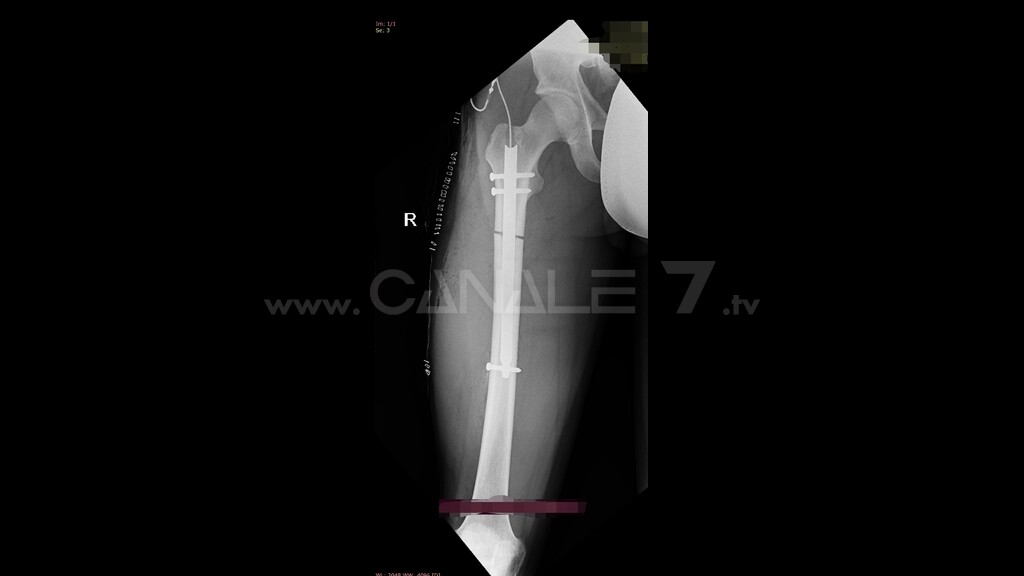

Un’operazione complessa e rara, a fronte di una diagnosi di Ipoplasia femorale congenita con una dismetria di 6 centimetri, in cui è previsto l’impiego di un chiodo endomidollare telescopico. Il dispositivo, realizzato in materiale biocompatibile, permette l’allungamento progressivo del femore di 1 millimetro al giorno e viene adoperato dal paziente stesso, in maniera del tutto autonoma, attraverso un sistema elettronico esterno che genera un segnale elettromagnetico inviato a un sensore impiantato sottocute.

In sostanza, ogni giorno il paziente azionerà direttamente una specie di “telecomando” che darà l’input al chiodo ortopedico telescopico, innescando così la crescita dell’arto. L’osteogenesi distrazionale, in virtù della rigenerazione ossea, permetterà così il recupero progressivo della dismetria in un tempo variabile, stimato in almeno due mesi in base al previsto allungamento di un millimetro al giorno, con concessione del carico completo per permettere la formazione di un callo osseo affidabile.